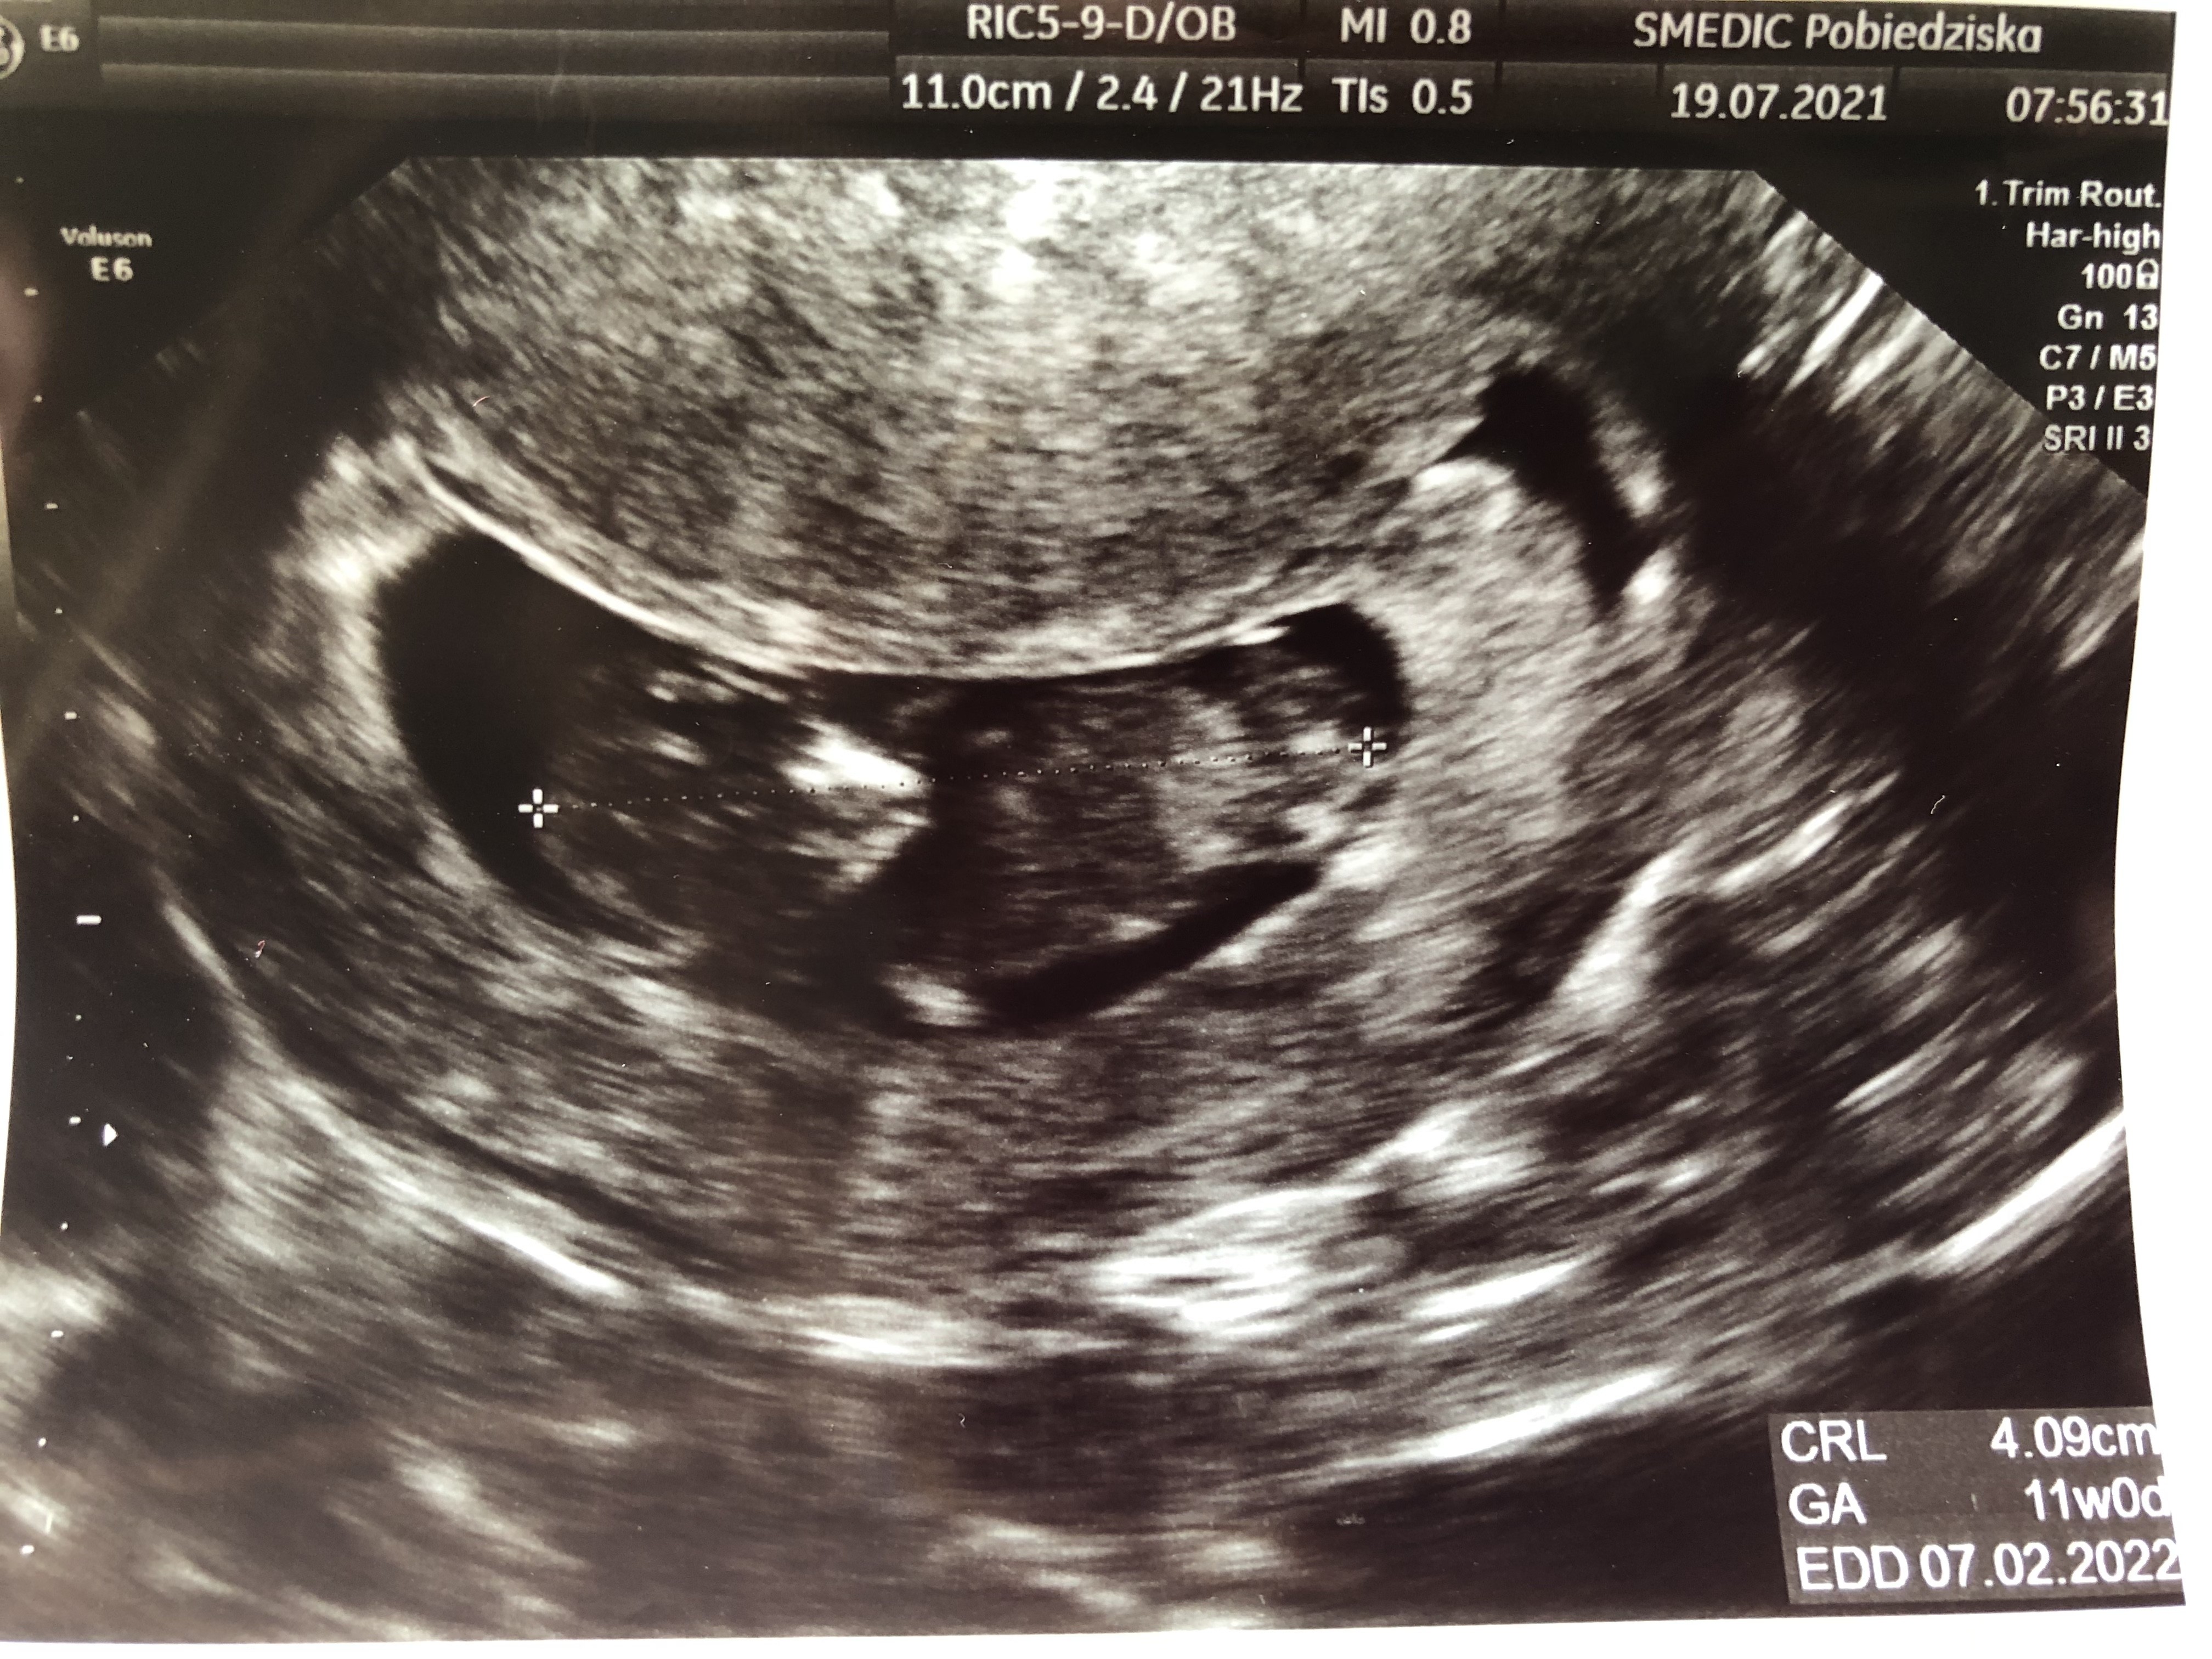

Przez to odkąd wiem o ciąży schudłam 4 kg. Żadnego dodatkowego brzuszka nie widzę, ale przy dotykaniu podbrzusza czuję, że tam gdzie zawsze było mięciutko jest jakby twardziutko